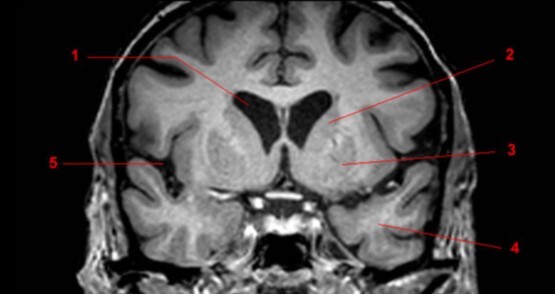

Label 1-3

Label 1-4

1-Lt Optic nerve

2-Optic chiasm

3-Rt Optic tract

Label 1,10,12

1=Lt cerebral peduncle (midbrain)

10=Interpeduncular cistern

12=Cerebral aqueduct

Label 7-11

7=Rt Internal carotid artery

8=Optic chiasm

9=Pituitary gland

10-Lt lateral ventricle

11=Lt Cavernous sinus